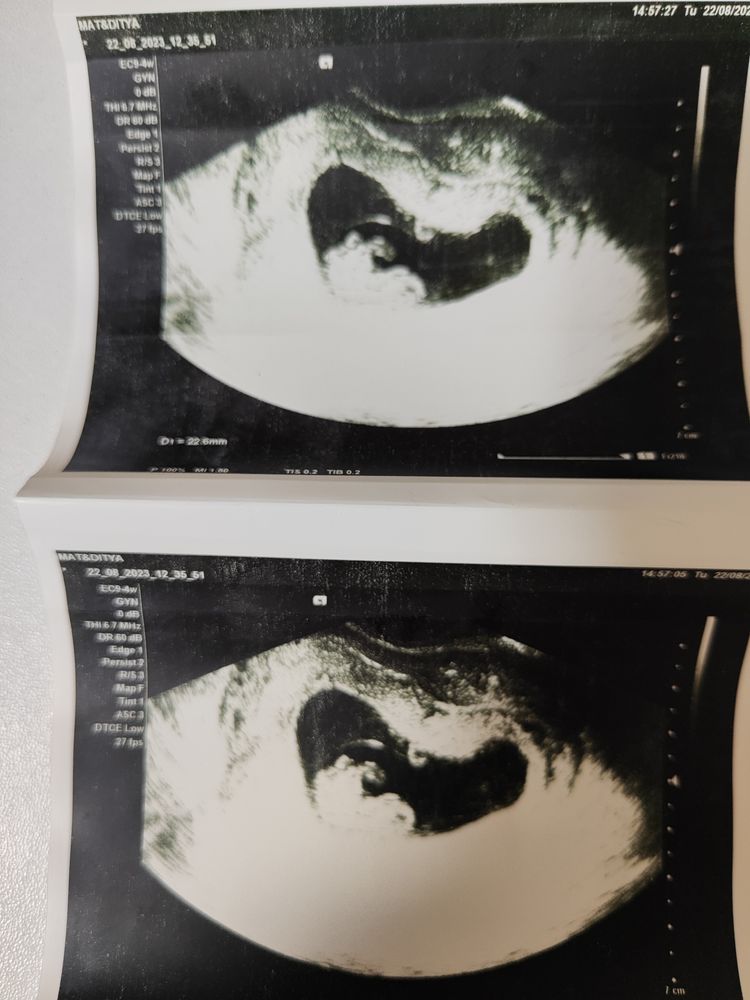

Дарина в Зачатие год Покидайте фото узи в 9 недель 🙏🏻 УЗИ Девочки у кого остались или есть фоточки покидайте пожалуйста! Хочу сходить в 9 неделек на узи, с монитором, хочется узнать как что там примерно видно будет Посмотрите еще 20 записей на эту тему Лучший ответ Елена 9н 2д двойня 02.11.2024 Ответить Отменить Ответить Таня Орозова 01.11.2024 Ответить Екатерина 01.11.2024 Ответить Екатерина Екатерина, чуть больше, 9,5 01.11.2024 Ответить Евгения 9+3 недели 01.11.2024 Ответить ЛисАлис 01.11.2024 Ответить Екатерина 01.11.2024 Ответить Екатерина Екатерина, 9 недель ровно, первое УЗИ 01.11.2024 Ответить Екатерина Екатерина, ножки попка к верху 😄 01.11.2024 Ответить Дарья 01.11.2024 Ответить Евгения Дарья , а вам делали трансвагинально или абдоминально? 01.11.2024 Ответить Дарья Евгения, трансвагинально . А вот 10 недель узи) 01.11.2024 Ответить Евгения Дарья , ух ты) а мне абдоминально делали😁 как в этот раз будут не знаю, пойду в другое место 01.11.2024 Ответить Евгения 01.11.2024 Ответить Мира В интернете нашла)) 01.11.2024 Ответить Девочки подскажите !! Пост нытья Чаты Беременных Выберите чат: Январята-2026 Февралята-2026 Мартята-2026 Апрелята-2026 Майчата-2026 Июнята-2026 Июлята-2026 Августята-2026